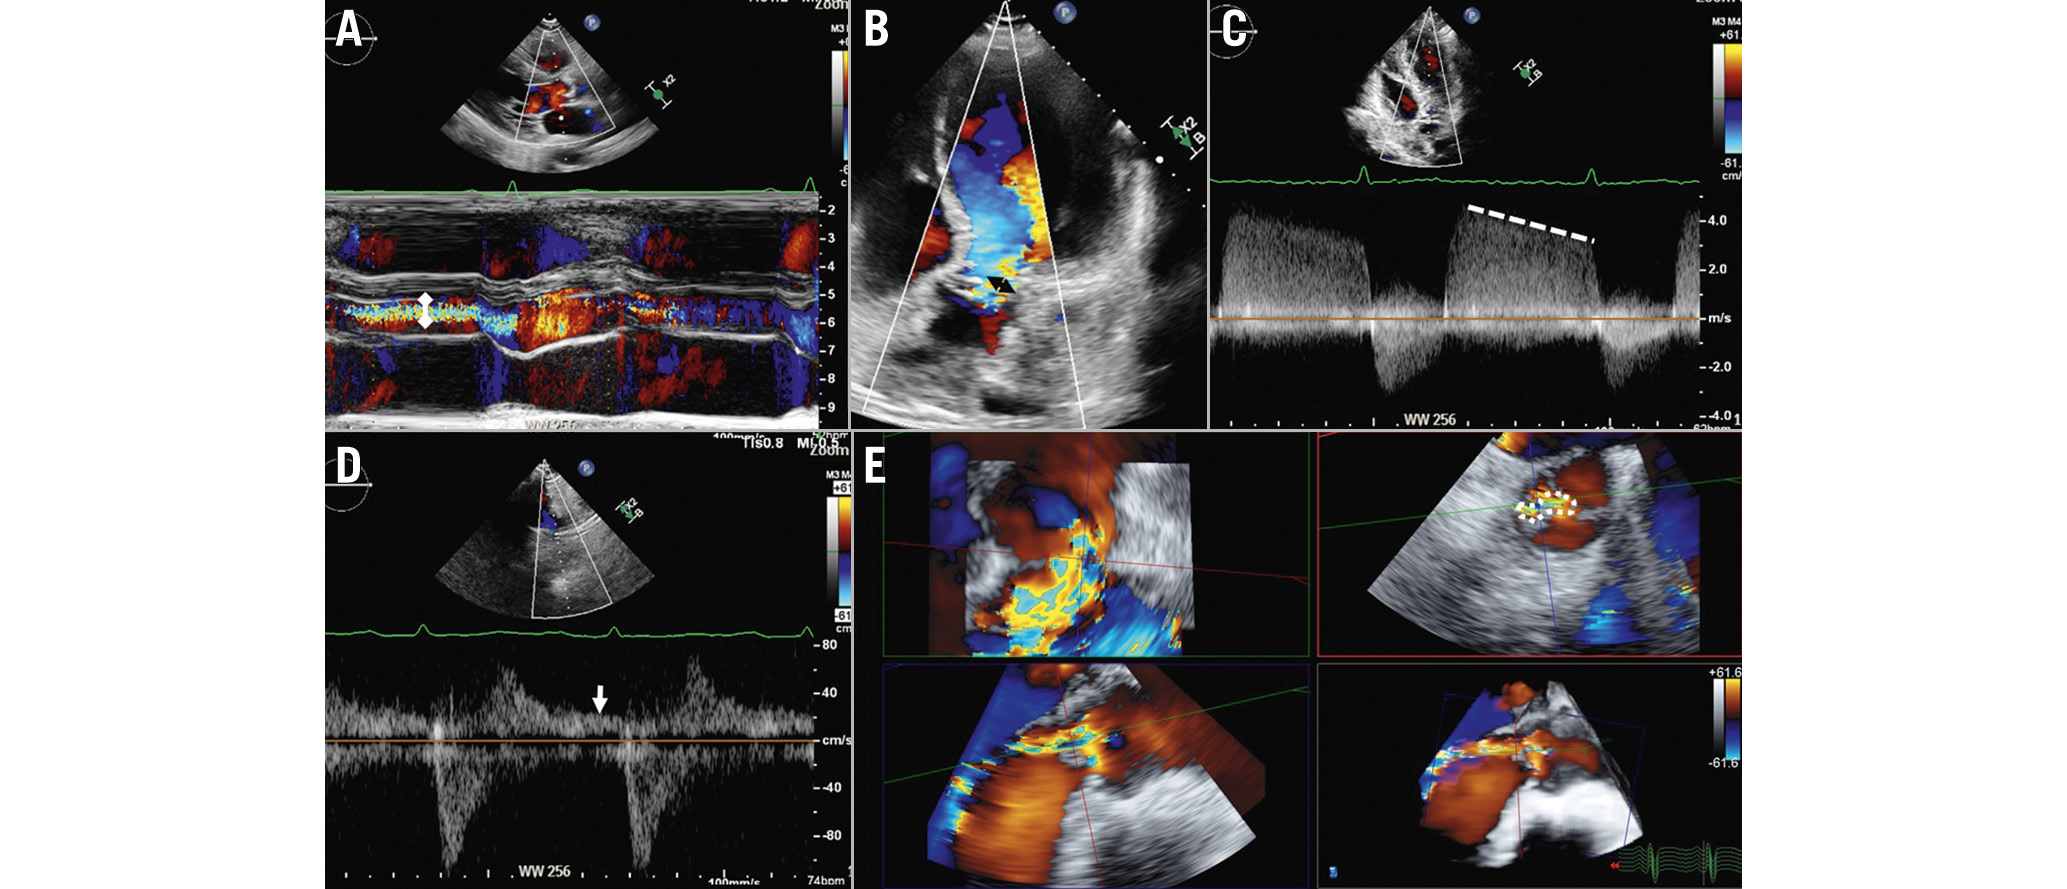

Qualitatively, severe AR is characterised by a large colour flow convergence zone, a dense signal of the continuous wave Doppler signal of the regurgitant jet and holodiastolic flow reversal in the descending aorta with an end-diastolic peak velocity of ≥20 cm/s (Figure 5). The presence of diastolic flow reversal in the abdominal aorta visualised from the echocardiographic subcostal view indicates acute, severe AR. Other methods to quantify AR include the measurement of the regurgitant volume by subtracting the pulmonic flow from the aortic forward flow, which requires a competent pulmonic valve, and the difference between the right and the left ventricular stroke volume obtained with planimetry, though it is an unreliable method when mitral or tricuspid regurgitation coexist.

Figure 5. Assessment of aortic regurgitation with echocardiography. The following parameters should be taken into consideration to assess the severity of aortic regurgitation: the ratio between the width of the regurgitant jet (double white arrowhead) and the diameter of the left ventricular outflow tract on colour M-mode of the parasternal long-axis view (A), the vena contracta as measured on the colour Doppler image acquired from the apical 5-chamber view (double black arrowhead; B), and the dense signal of the regurgitant jet on a continuous wave Doppler image where the pressure half-time can be measured (C, dotted line). D) Diastolic flow reversal obtained with pulsed wave Doppler from the suprasternal view (white arrow). Three-dimensional colour Doppler transoesophageal echocardiography permits the measurement of the anatomical regurgitant orifice area (E, dotted encircling line) by aligning the multiplanar reformation planes across the vena contracta.